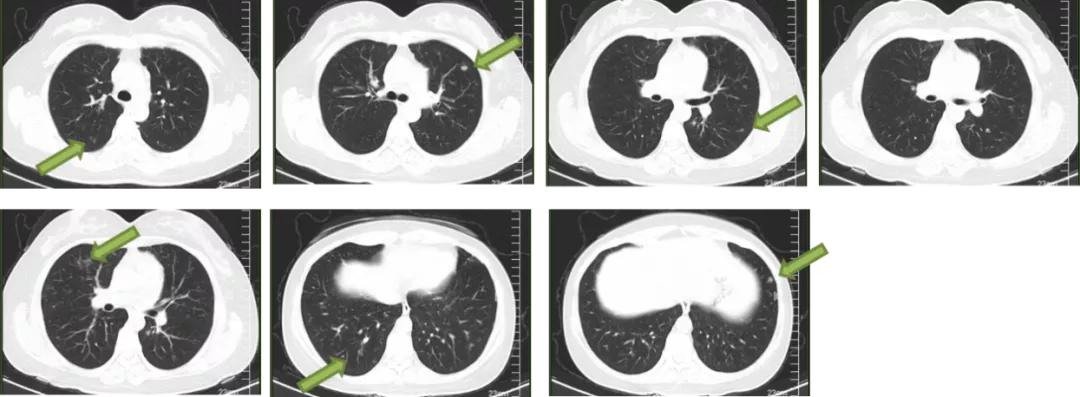

4月28日行胸部CT显示两肺多发结节(最大直径0.8cm),性质待定;纵隔小淋巴结,两肺局部少许炎症。

图2:胸部CT(2020.4.28)